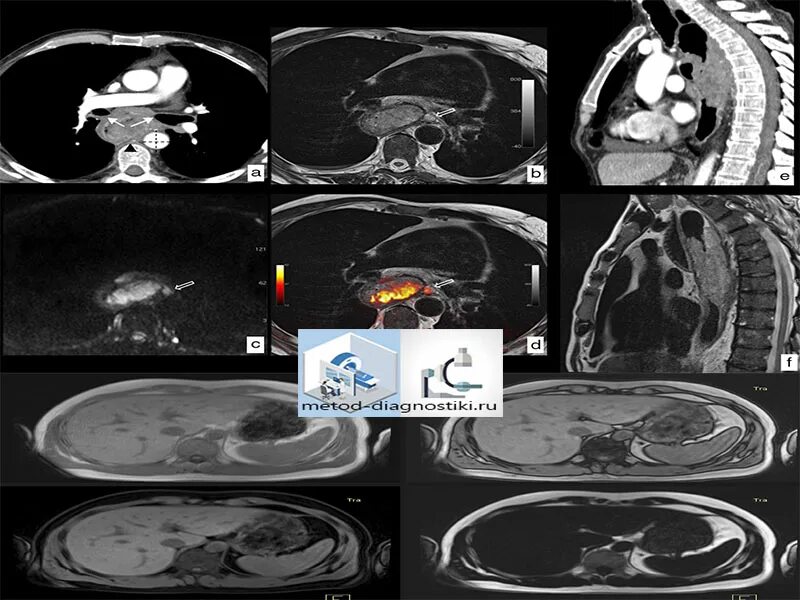

Обследование кт кишечника